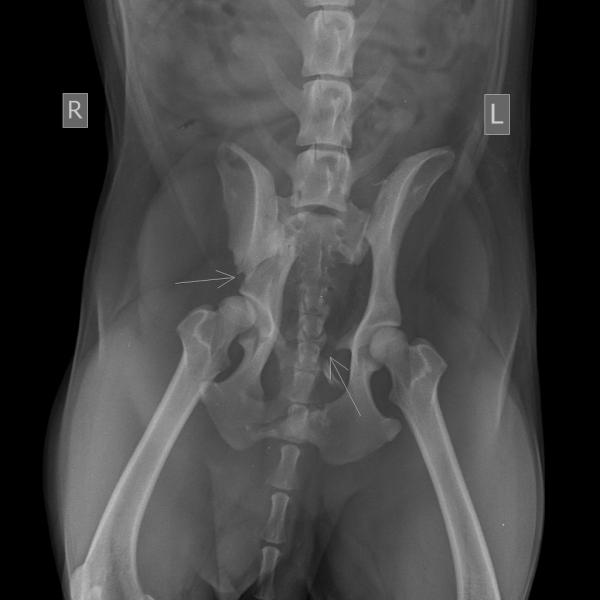

Las personas encargadas de diagnosticar la fractura, clasificarla y posteriormente instaurar el tratamiento pertinente son el personal veterinario. Al acudir a consulta y utilizar exámenes complementarios como los rayos X, se puede obtener mayor información del paciente y la lesión, logrando así un mejor diagnóstico por parte del médico/a.

Pero, ¿puede vivir un perro con la cadera rota? Dependerá del tipo de fractura que tenga y a qué nivel de la cadera esté. En el caso de la luxación de cadera en perros, no siempre se necesitará una operación, pero sí suficiente reposo para que pueda sanar correctamente. Cuando hablamos propiamente de una fractura, siempre tienen que ser atendidas de manera terapéutica y/o quirúrgica. Es recomendable hacer exámenes pertinentes como rayos x, que permitirán determinar el tipo de fractura que tiene tu mascota.

Hola buenas noche hoy atropellaron a mi perrita tiene 4 meses le sacaron radiografía y le inyectaron antibióticos y antiinflamatorio solo eso necesito si me pueden orientar tengo esta radiografía

Ayer atropellaron a mi perro y tengo estas radiografías, el veterinario dice que hay que operarlo pero con él cuesta mucho la operación, ustedes creen que con buen cuidado pueda curarse y caminar normal en unos meses ?